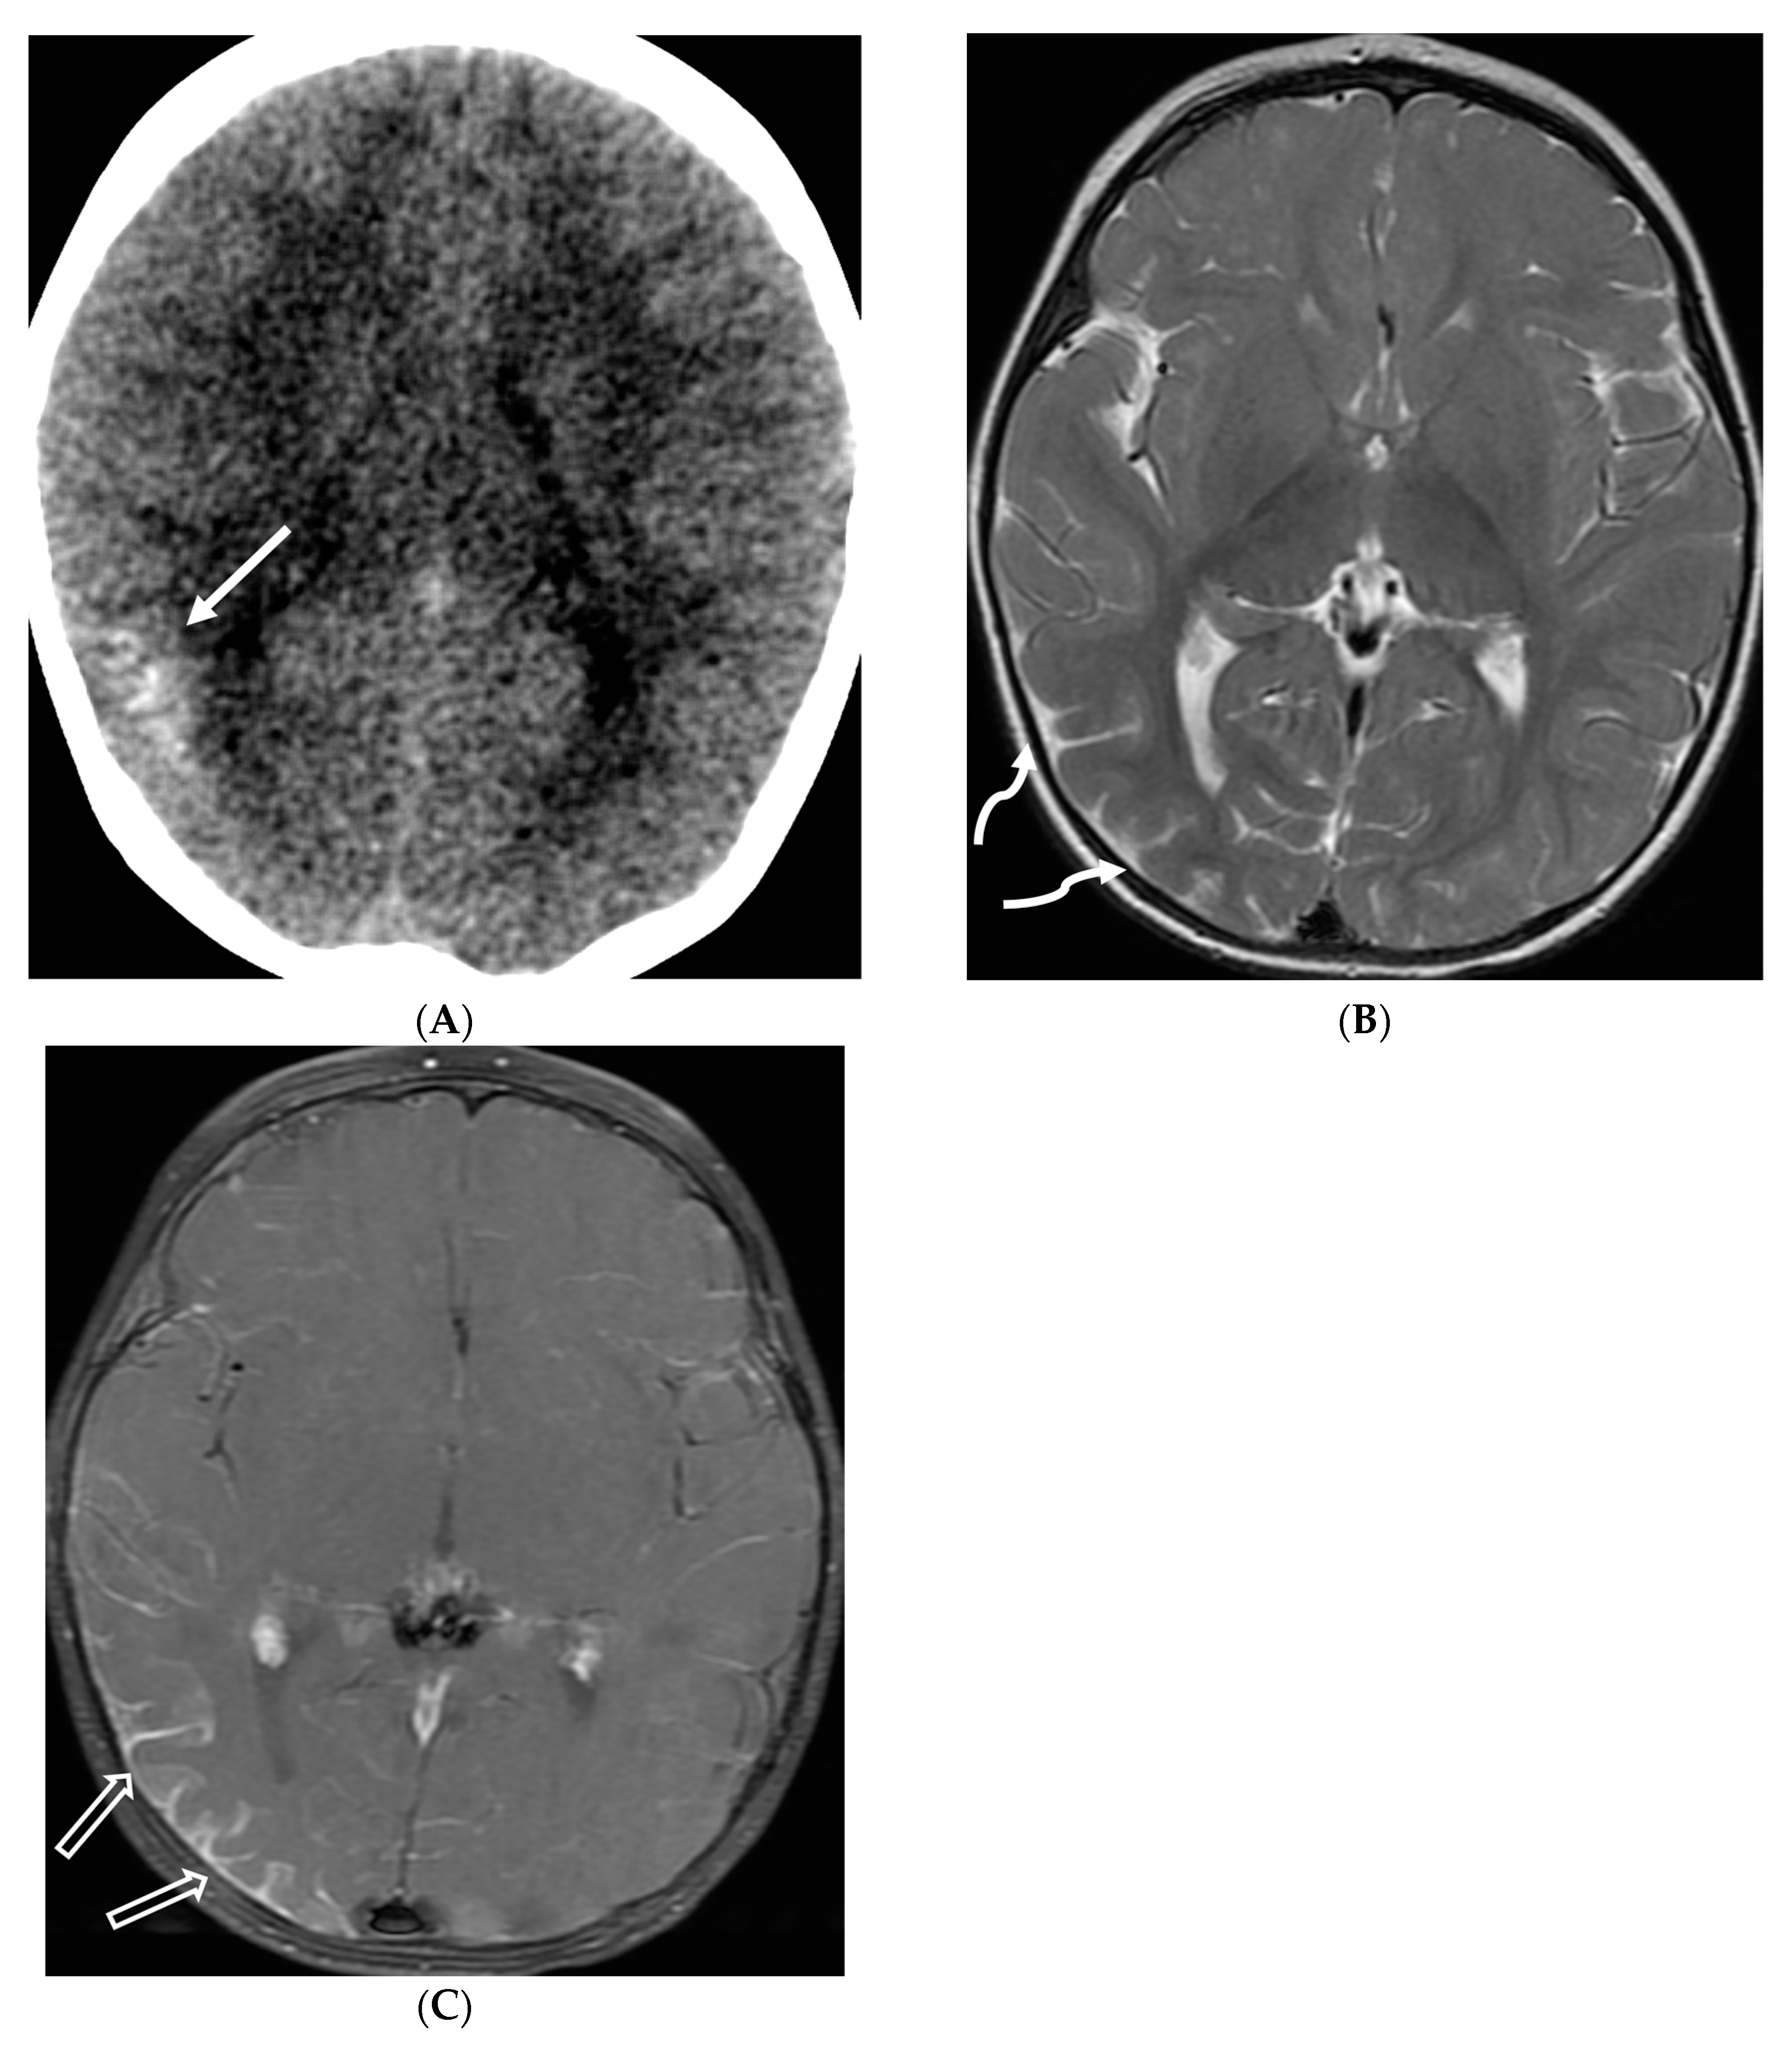

E. coli is another common neonatal and infantile cause of bacterial meningitis. There is characteristic diffusion restriction in the extra-axial collections along with ventriculomegaly and/or ventriculitis [74]. To note, extra-axial empyema is also common with S. pneumoniae, but occur in an older age group. Serratia marcescens and Citrobacter are two uncommon pathogens causing meningitis in neonates with fulminant disease course. They lead to large parenchymal abscesses with striated appearance on T2W images and foci of susceptibility. N. meningitidies causes typical gyriform cortical enhancement consistent with cerebritis predominantly involving the occipital lobes (Figure 12) [74].

Figure 12.

Axial DWI (A), axial SWI (B), sagittal T2 (C), axial ASL (D) and coronal T1 post contrast (E): 11-day-old female presented with seizures and lethargic. Restricted diffusion is noted in the sulci along the bilateral frontal convexities, concerning for meningitis (arrows). Curvilinear susceptibility in the extra-axial spaces of bilateral frontal convexities, consistent with thrombosed cortical veins (curved arrows). Cortical T2 hyperintensity is seen in the bilateral frontal and parietal lobes with corresponding hyperperfusion in keeping with extensive cerebritis (dashed arrows). Diffuse leptomeningeal and pachymeningeal enhancement is seen (open arrows). Overall features represent meningitis and cerebritis. Cerebrospinal fluid analysis: Group B streptococcus.